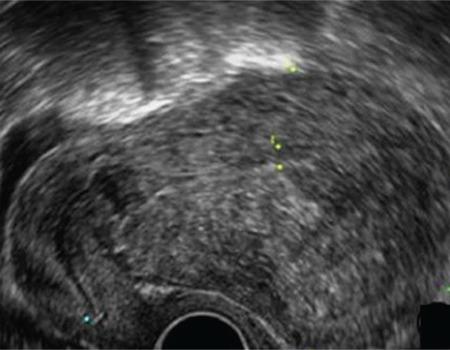

Endometriosis is one of the most common benign diseases in women of reproductive age. Nearly all gynecological offices and clinics will contain patients with endometriosis; the frequency and severity of the disease will vary from one setting to another. Adjoining specialties, such as internal medicine, general medicine, surgery, urology, orthopedics, neurology and psychosomatic medicine, will be challenged directly or indirectly by various forms of endometriosis and its sequelae. The disease is characterized by pelvic pain, dysmenorrhea, dyspareunia and sterility. Even now, several years may elapse between the onset of the disease and its diagnosis. The diagnosis of endometriosis is complicated by the diversity of the symptoms. A precise documentation of the patient’s medical history and thorough diagnostic procedures are essential to establish a robust diagnosis. This article will discuss the perioperative considerations, diagnosis and treatment of endometriosis.